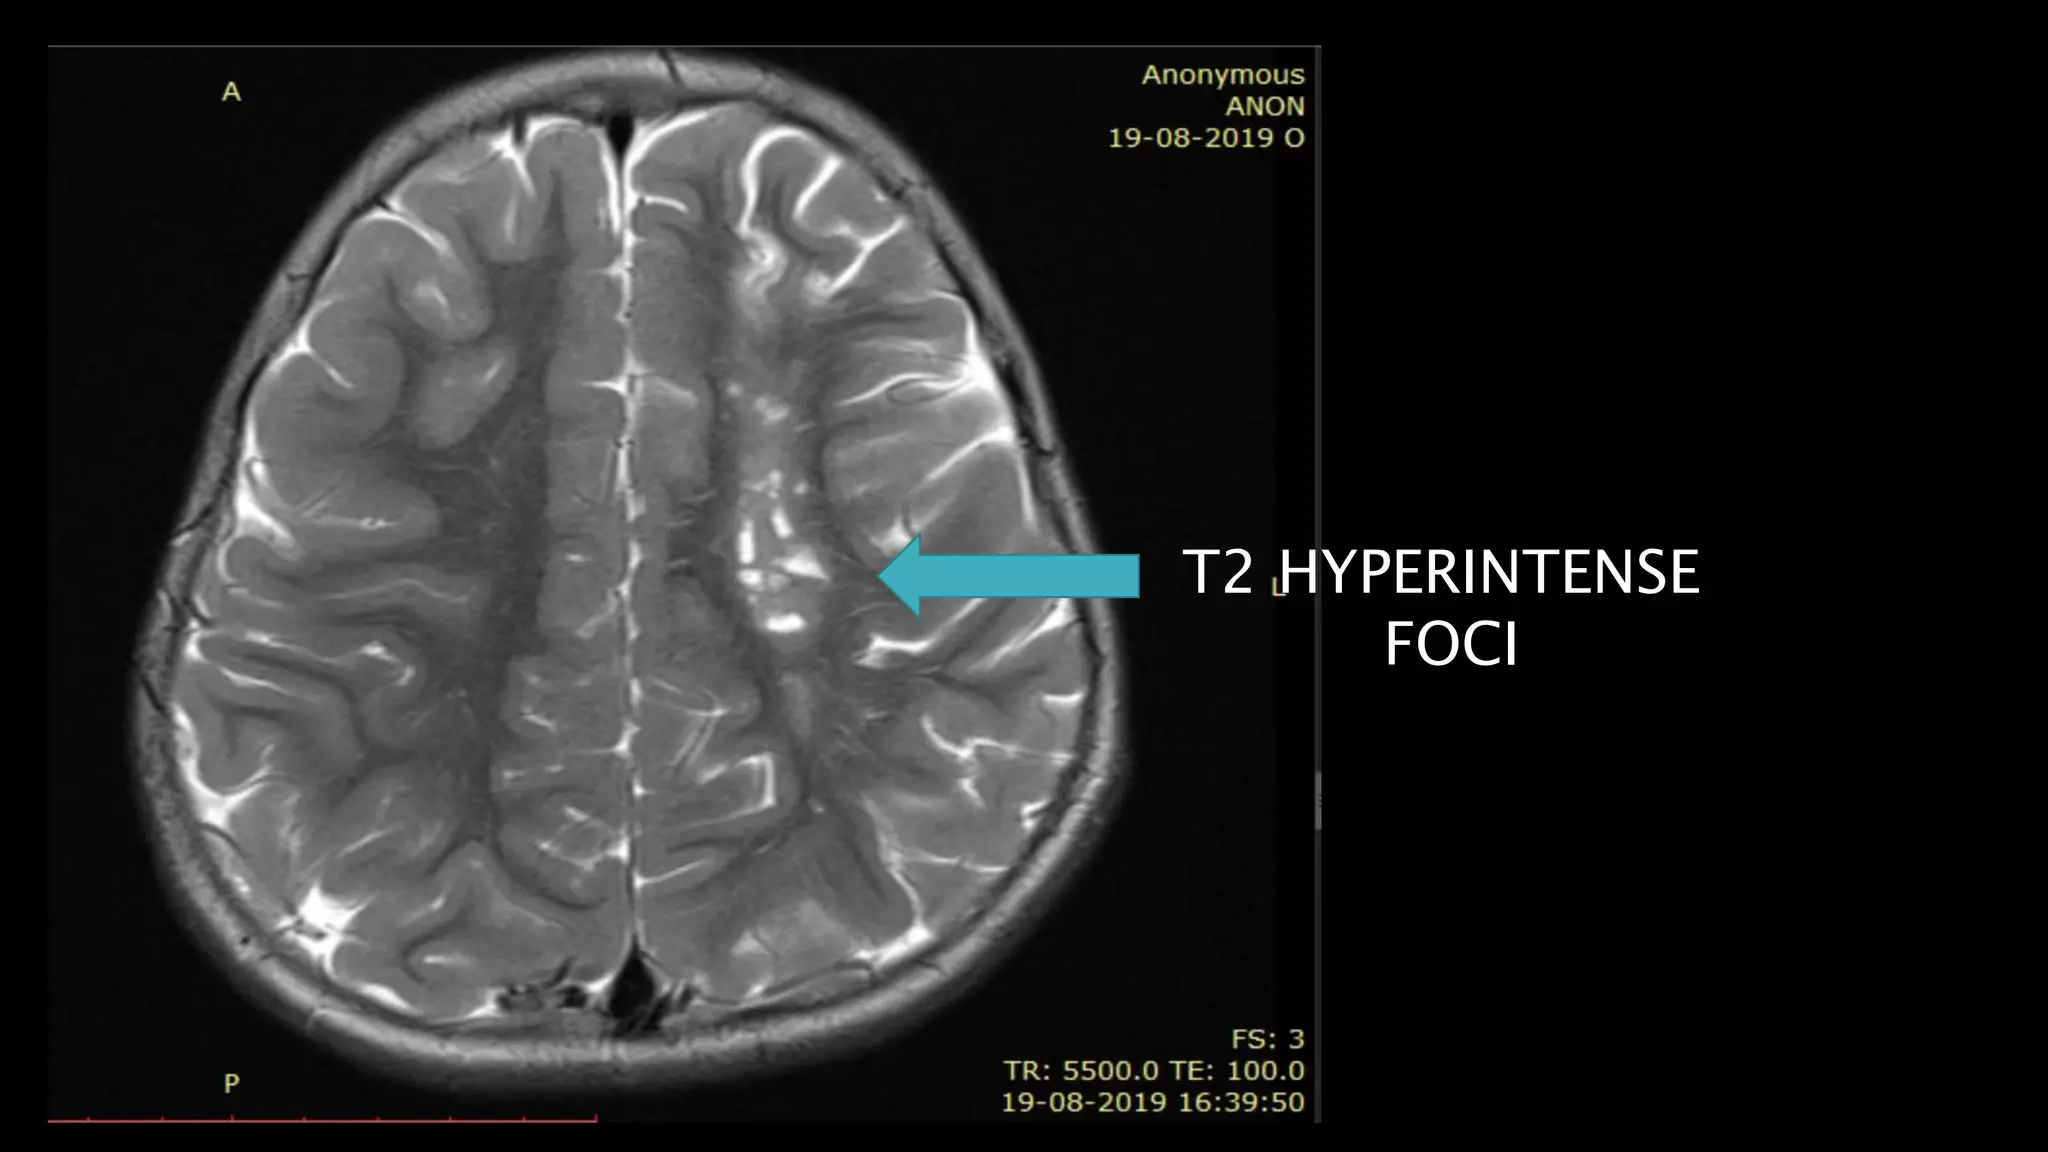

T2 HYPERINTENSE

FOCI

HYPOINTENSE FOCI

WITH MARGINAL

HYPERINTENSITY

• #100 Chronic infarct Follows CSF signal

• #102 This is the saggital T1WI of a showing multiple oval T1 hypointensities in left centrum semiovale and frontal white matter in a in a child with homocystinuria

• #103 Which apppeaer hyperintense on T2WI

• #104 And shows signal suppression on FLAIR in the centre with marginal hyperintensity

• #105 There is no diffusion restriction on DWI and ADC map s/o chronic infarcts with glioenccephalomalacic changes.